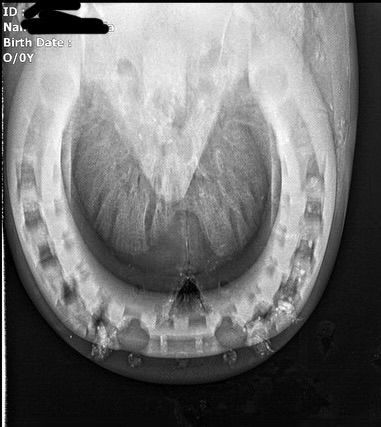

If your horse is lame, the first step is to notify your veterinarian. Once an abscess is confirmed or if your veterinarian recommends treating it as such, here is a step-by-step protocol on management. Radiographs are always appreciated to see the extent of the infectious tract or where it might possible release.

Other possibilities that can contribute to chronic abscessing (esp. if on the same foot) would be a keratoma. A keratoma is a benign growth, or a disorganized collection of keratin, that imposes on the coffin bone. They can cause lameness and chronic abscessing. These are typically visible on the solar aspect of the hoof, as they tend to create a deviation of the sole into the whiteline. Your hoof care provider should be able to identify this, though a series of radiographs and veterinarian assessment are needed to confirm. Note: not all keratomas are problematic, I have many horses on my books that don’t experience issues from them. They’re typically not a problem until they’re a problem.